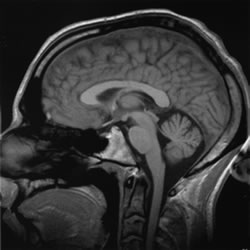

It’s all to do with our brains (image courtesy Wikimedia)